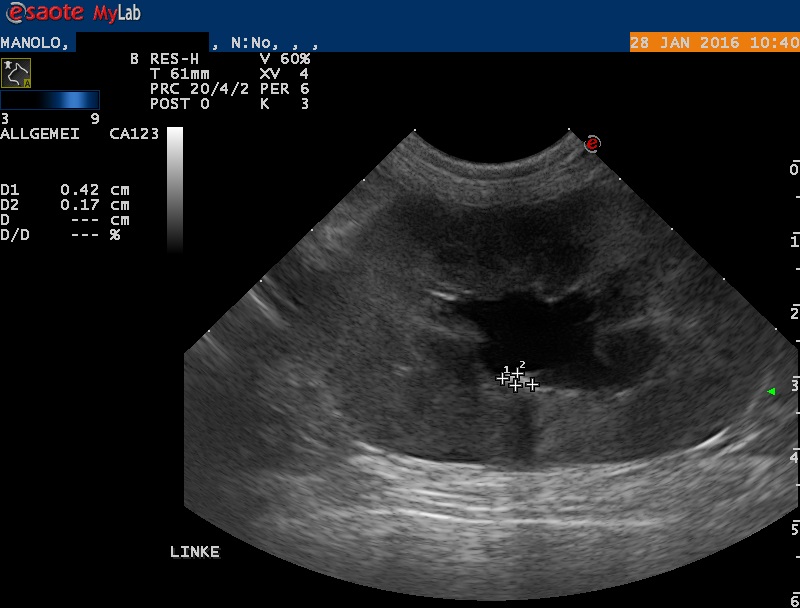

Der Bauch von Manolo wird mittels Ultraschall untersucht: Die rechte Niere erscheint klein und weist eine veränderte Architektur auf. Die linke Niere ist deutlich vergrössert; das Nierenbecken ist erweitert, und auch der ableitende Harnleiter ist deutlich erweitert. Im Nierenbecken findet sich ein kleiner Nierenstein von ca 4x2x2 mm Grösse. Mittels steriler Punktion wird Urin aus der Harnblase entnommen - im Urin befinden sich grosse Mengen rote und weisse Blutkörperchen sowie Baktieren, auch ist der Harn wenig konzentriert.

Die Erweiterung des Beckens und des Harnleiters (Ureter) der linken Niere weisen auf eine Blockade des Harnleiters hin, welcher den Urin von der Niere in die Blase transportieren sollte. Durch die Blockade wird Urin gestaut und das Nierenbecken und der vor der Blockade liegende Teil des Ureters quasi "aufgeblasen". Die Folge ist eine Funktionsstörung der Niere, wodurch sich die Nierenwerte im Blut erhöhen. Die beobachteten Veränderungen der rechten Niere könnten darauf hinweisen, dass auch dieses Organ in der Vergangenheit eine ähnliche Schädigung erlitten hat - dadurch, dass die linke (damals gesunde) Niere noch normal funktionierte, wurde diese Schädigung möglicherweise nicht bemerkt.

Harnleiterblockaden sind bei Katze nicht allzu selten. In vielen Fällen ist ein kleiner Nierenstein, welcher aus dem Nierenbecken abgegangen und im Harnleiter stecken geblieben ist, die Ursache des Problems. Bei Manolo wurde allerdings kein solcher Stein gefunden (obwohl im Ultraschall ein kleiner Nierenbeckenstein entdeckt wurde) - offenbar bewirkte eine möglicherweise infektionsbedingte Schwellung des Harnleiters die Blockade.